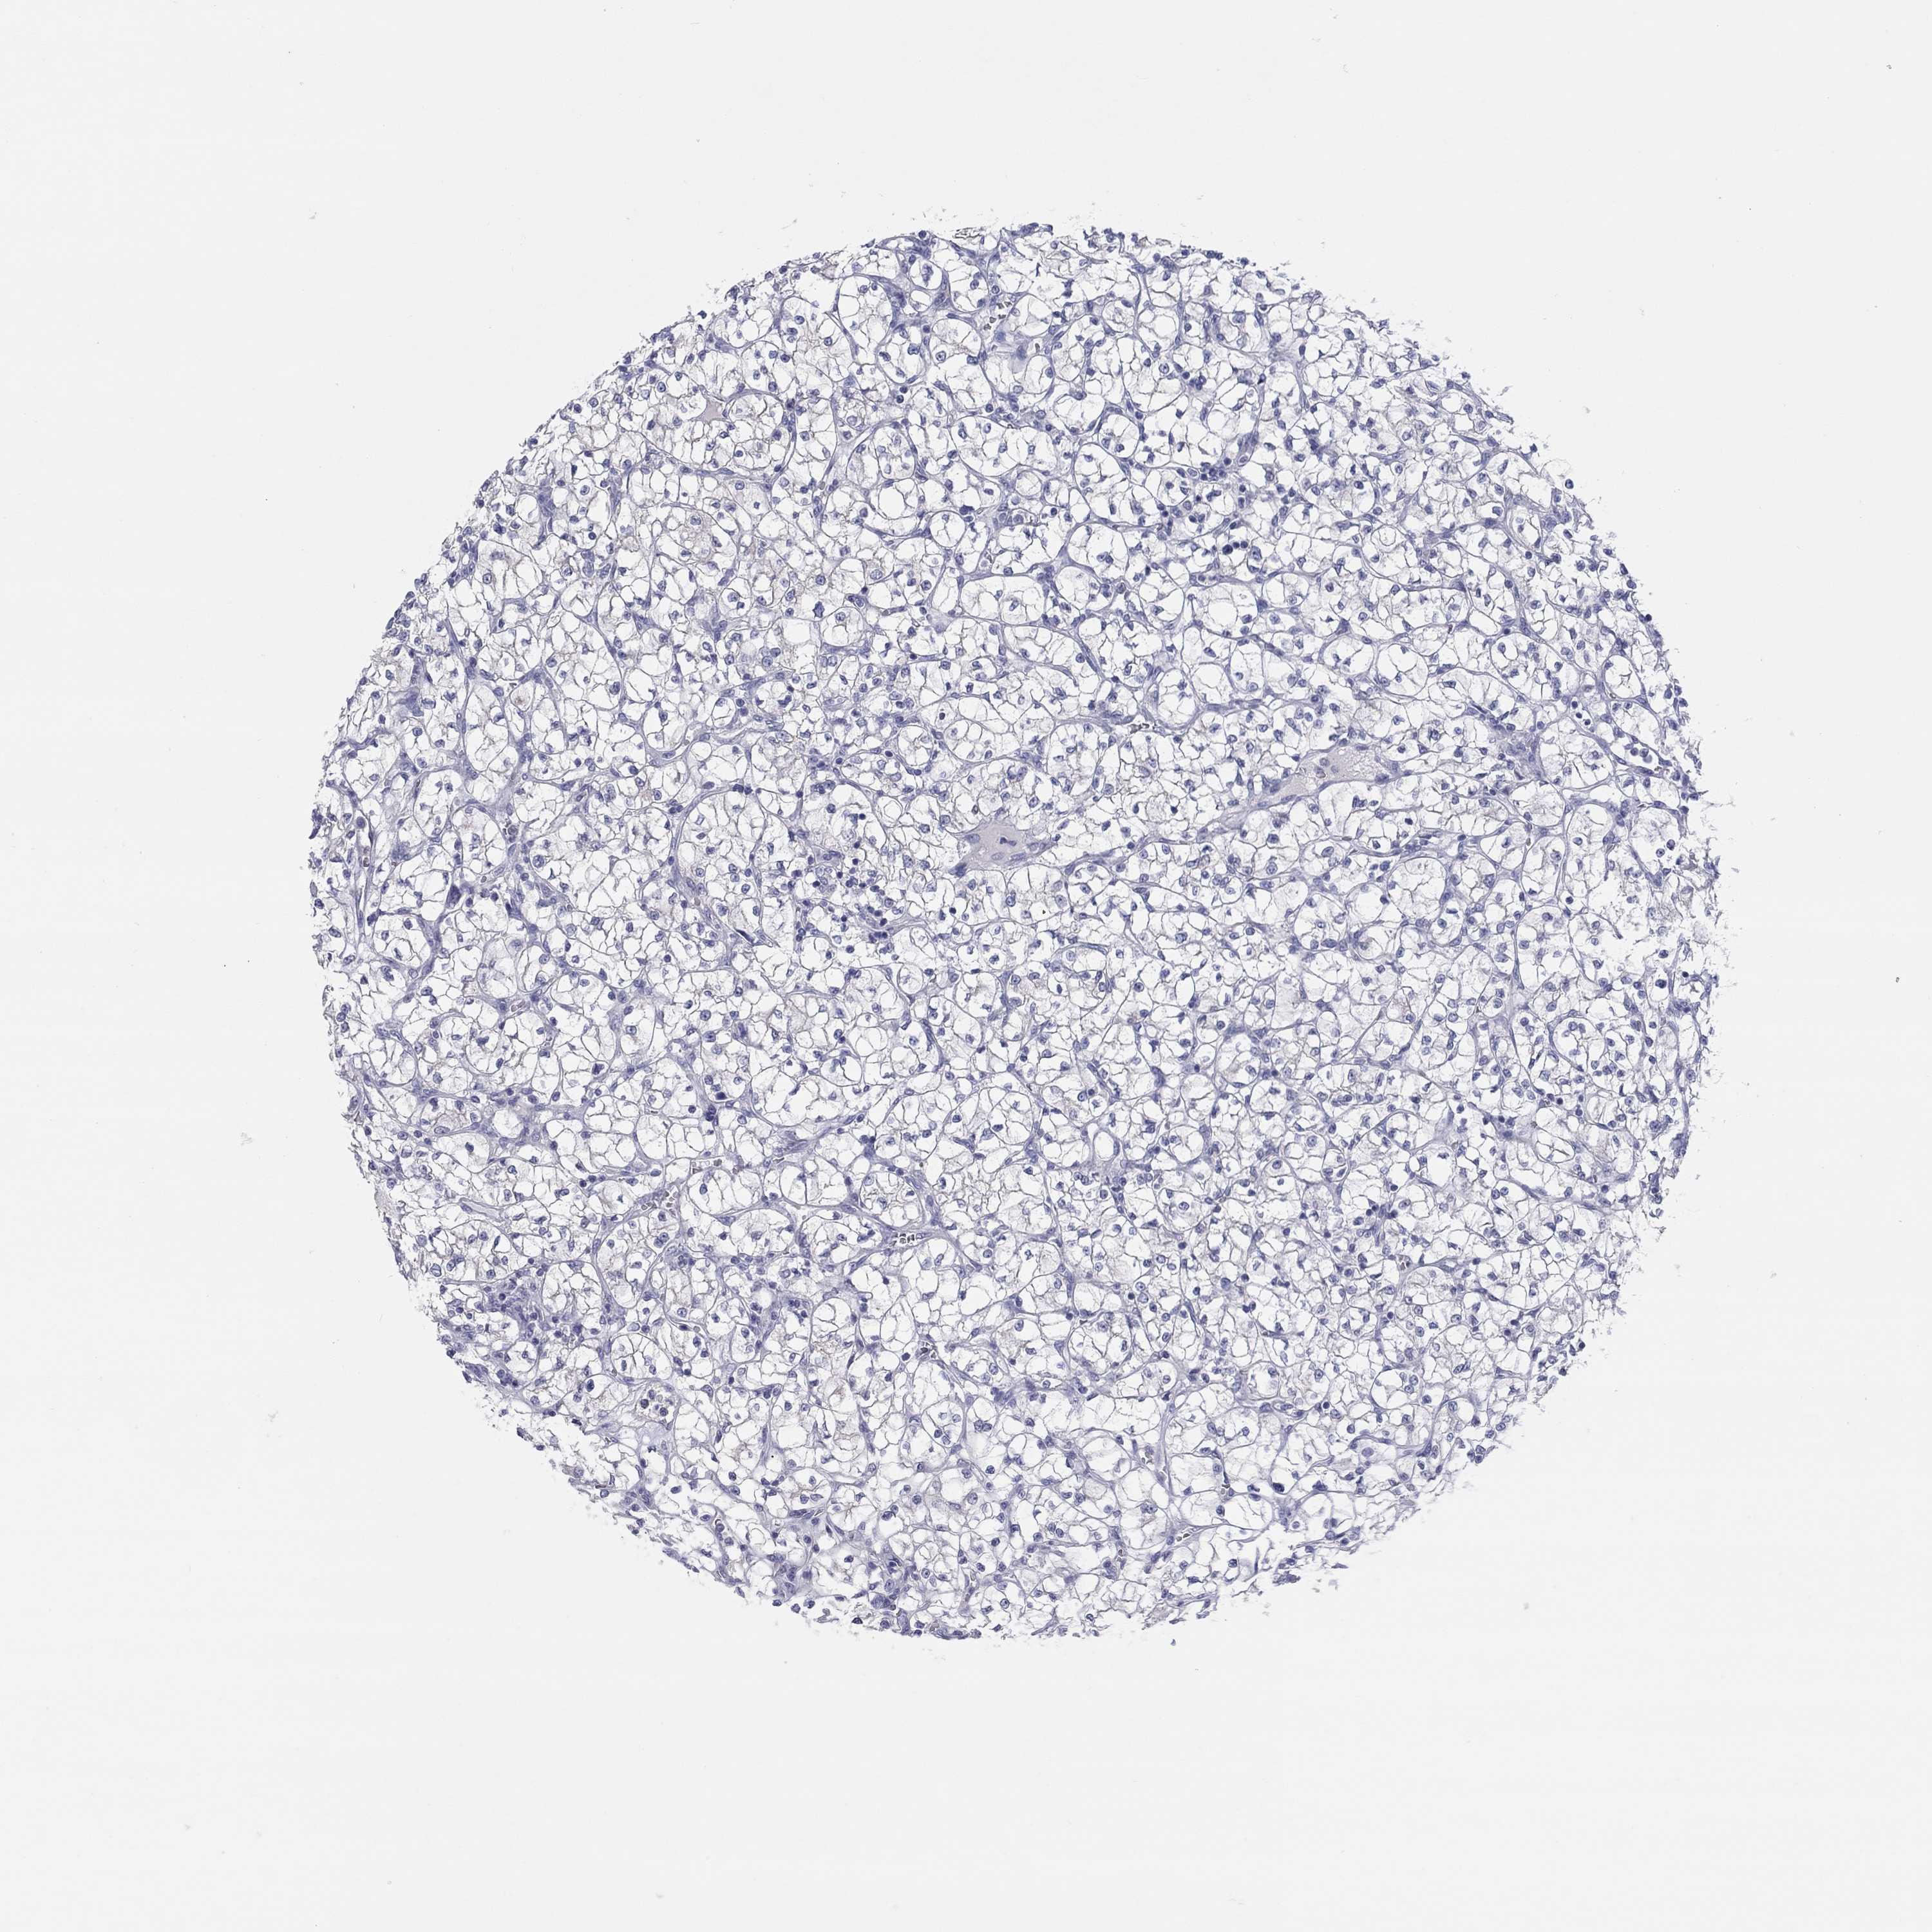

CANCER RENAL CANCER Show tissue menu

KICH TCGA KIRC TCGA KIRC VALIDATION KIRP TCGA PROTEIN RCC CPTAC PROTEIN EXPRESSION